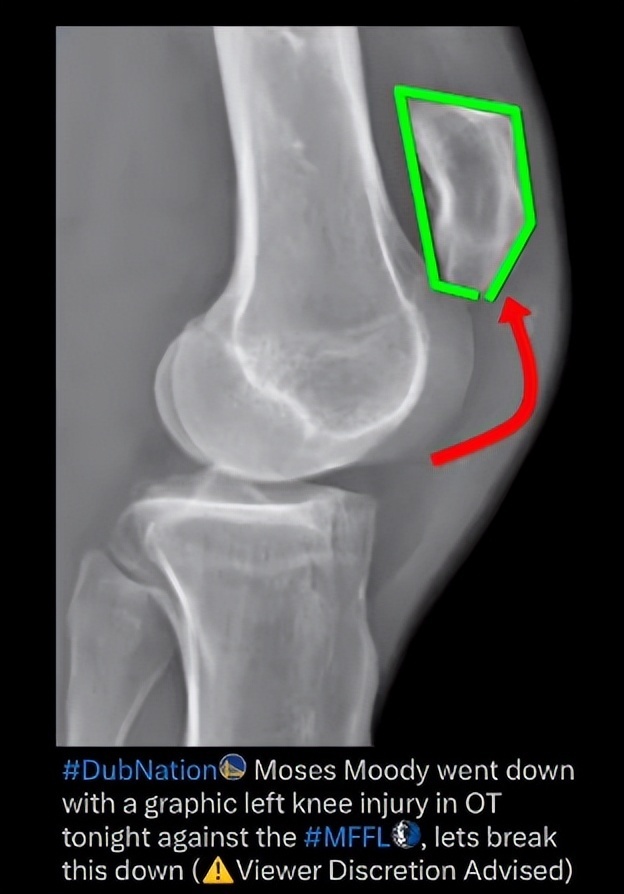

北京时间3月25日,金州勇士队官方发布了摩西-穆迪的MRI检测报告,经过核磁共振后,确定穆迪是左膝髌腱撕裂,他将在本周晚些时候接受手术,并将缺席25-26赛季剩余的比赛。穆迪是在对阵独行侠比赛加时赛还剩58.5秒一次快攻中无对抗受伤,恢复时间在9-12个月。

医学专家Brian Sutterer在个人的播客详细的分析了穆迪受伤的瞬间,他最终解析的结果是髌腱断裂而非向外侧移位的髌骨脱位,从机制上看当肌腱在被拉伸(离心)状态下,突然承受强烈收缩(向心),容易在极限负荷下发生断裂,这一点与跟腱断裂的受伤模式类似。

所以最终穆迪的诊断结果是左膝髌腱撕裂已经是万幸,因为这两种诊断结果会完全不同。正如科尔所说:核磁共振检查结果是干净的,是(髌腱)的问题。软骨和骨头都没有受损,这算是好消息。这也意味着手术相对比较基础。